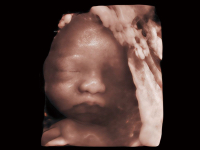

睿顏成像

多光源成像